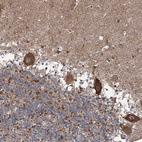

Immunohistochemical staining of human Cerebellum shows strong cytoplasmic positivity in Purkinje cells.